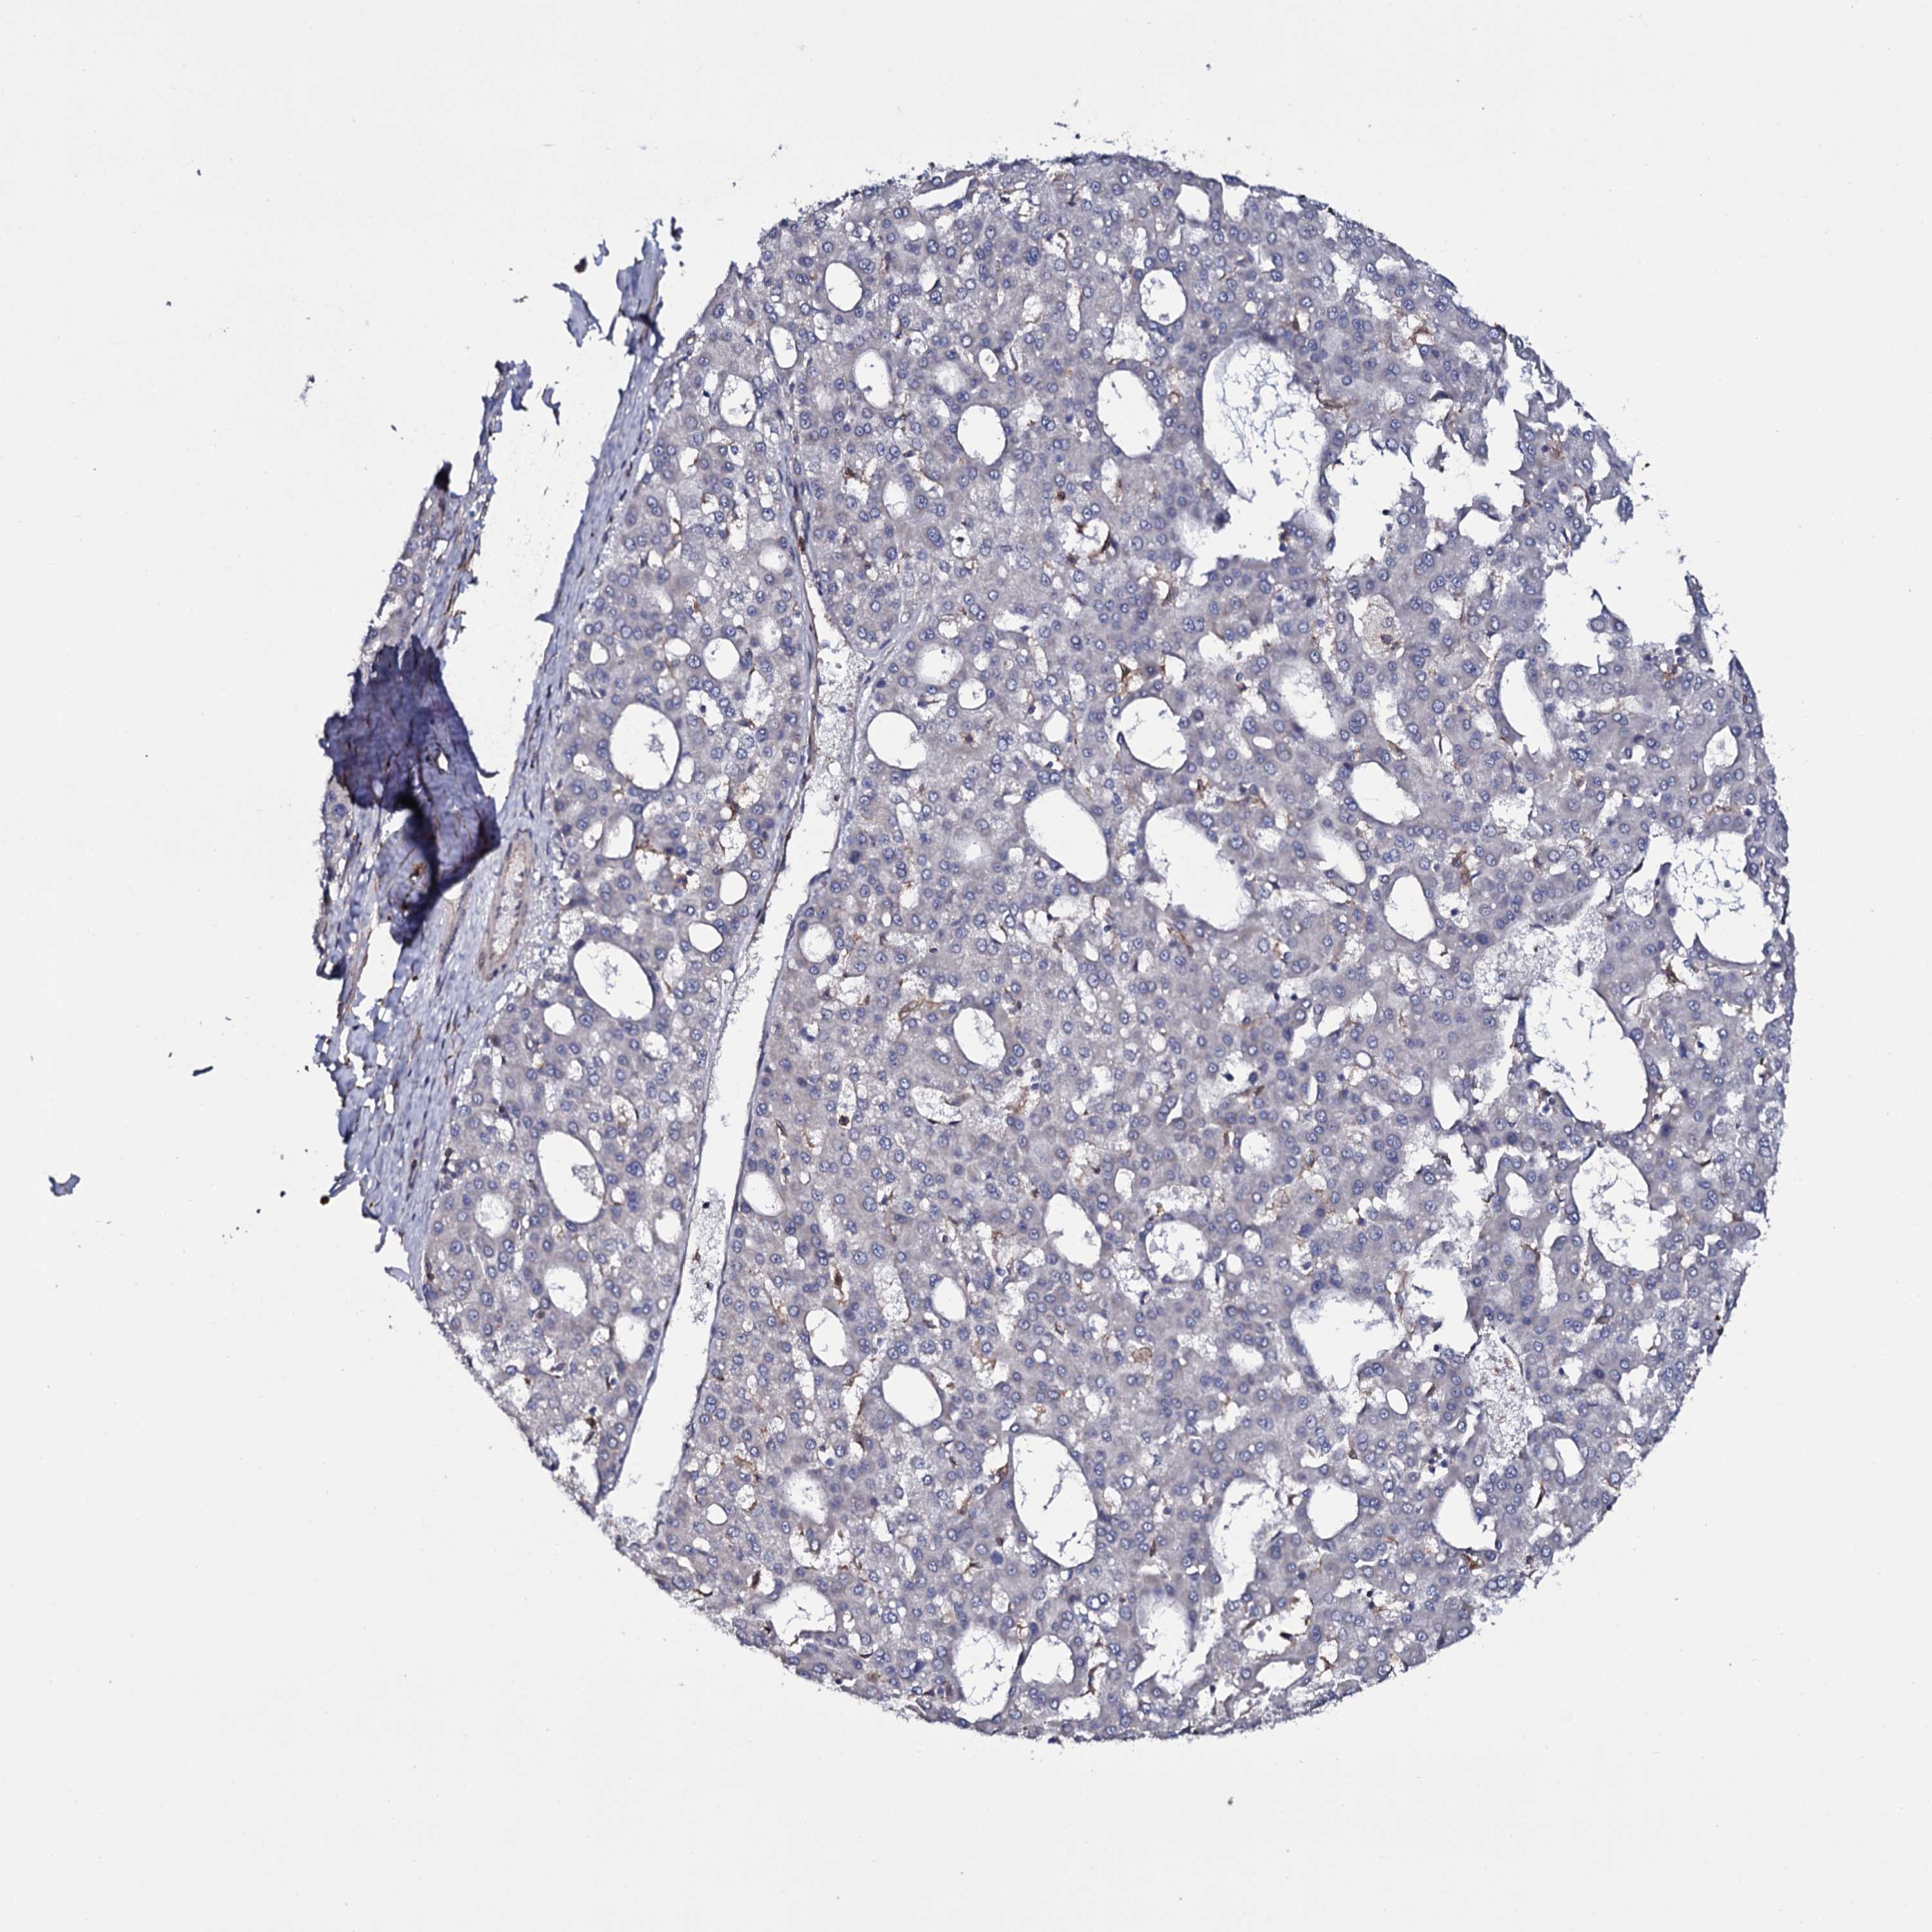

LIVER CANCER - Protein expressioni

A mouse-over function shows sample information and annotation data. Click on an image to view it in a full screen mode. Samples can be filtered based on level of antibody staining by selecting one or several of the following categories: high, medium, low and not detected. The assay and annotation is described here.

Note that samples used for immunohistochemistry by the Human Protein Atlas do not correspond to samples in the TCGA dataset.

Antibody stainingi

Antibody staining in the annotated cell types in the current human tissue is reported as not detected, low, medium, or high, based on conventional immunohistochemistry profiling in selected tissues. This score is based on the combination of the staining intensity and fraction of stained cells.

Each image is clickable and will lead to virtual microscopy that enables deeper exploration of all samples and also displays staining intensity scores, fraction scores and subcellular localization as well as patient and tissue information for each sample.

Antibody HPA039806

Antibody HPA040369

Staining

High

Medium

Low

Not detected

Intensity

Strong

Moderate

Weak

Negative

Quantity

>75%

75%-25%

<25%

None

Location

Nuclear

Cytoplasmic/membranous

Cytoplasmic/membranous,nuclear

Cholangiocarcinoma

Carcinoma, Hepatocellular, NOS